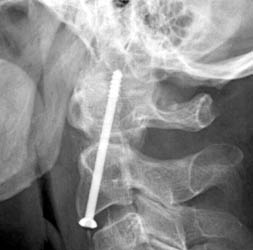

Screw Extending in Spinal Canal

65-year-old

male with a history of a fall at home with a workup that revealed a fracture of

the odontoid process. The

fracture was a posterior oblique type with an 8.0 mm posterior displacement.

The patient was neurologically intact and was kept in an Aspen collar at

all times prior to surgery. Given

the amount of displacement of the odontoid process and the patient's age and

reluctance to wear a halo, it was decided that an odontoid screw would be a good

option for this patient.

Lateral

radiograph obtained one day after surgery to assess for adequacy of

reduction and screw placement. The

film shows a threaded fixation screw coursing from the inferior endplate

of C-2 up through the tip of C2 with only two of the threads actually

within cortex with at least 8 mm of hardware protruding beyond the cortex

of C2 superiorly and the degree of protrusion posteriorly into the canal

appears to be 5 mm at its greatest extent.